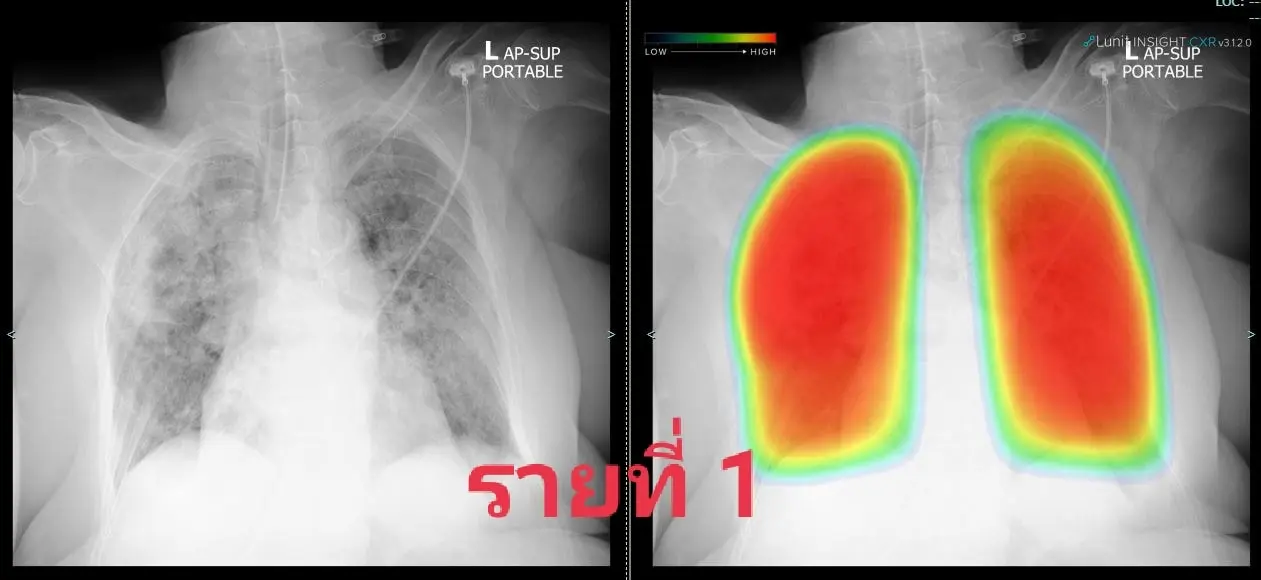

1. หญิง 84 ปีเดิมแข็งแรงดี

ทั้งสามคนอยู่ในพื้นที่ท่าพระ-ภาษีเจริญ โดยติดเชื้อกันส่วนใหญ่หรือทั้งครอบครัว พวกเขามารพ.ศิริราชด้วยอาการของปอดอักเสบโควิดรุนแรง รายแรกต้องใส่ท่อช่วยหายใจขณะนำส่ง รายที่สองใส่ทันทีเมื่อถึงรพ. ส่วนรายที่สามใช้ไฮโฟลว์ได้พักหนึ่งแล้วไม่ไหวต้องใส่ท่อ

ทั้งสามคนต้องรอเตียงย้ายเข้าไอซียูโควิดกันไม่น้อยกว่า 12 ชม. โชคดีว่าทีมเราเอาท่อช่วยหายใจผู้ป่วยออกได้สี่คนในช่วงสองวันนี้และย้ายออกไปได้สามคน จึงทยอยรับทั้งหมดเข้ามาไอซียูโควิดที่ทีมเราดูแลได้ แต่หากมีรายแบบนี้มาอีกคงหาจังหวะเหมาะเจาะเช่นนี้ไม่ได้อีกแล้วลองดูเอกซเรย์ปอดกันหน่อย พบมีฝ้าขาวเวอร์กระจายทั่วปอดในทุกคน จนเจ้า AI ที่ช่วยงานเรายังให้สีแดงแจ๋บ่งถึงรุนแรงน่ากลัวมาก